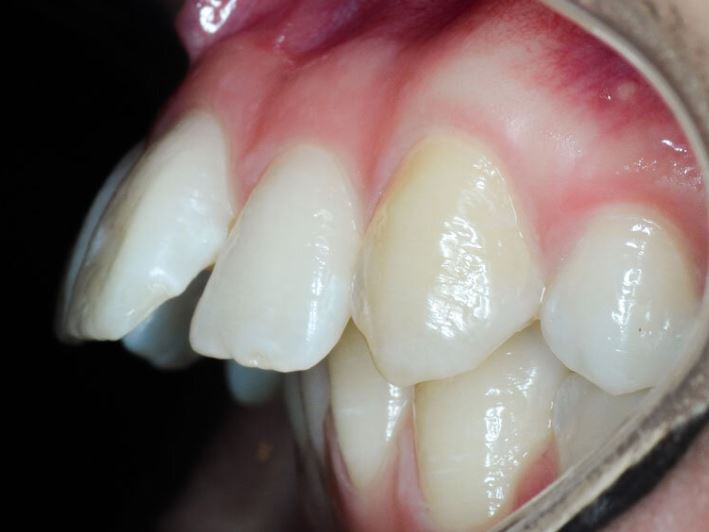

Недавно сделал с двух сторон сверху.

У меня уже сильно оголились + из-за брекетов убыль костной ткани.

Полностью закрыть не удалось, но ткани десны утолщили, потому процесс должен как минимум замедлиться.

За счёт хорошей гигиены кариеса нет.

Кстати сами смотрите свои снимки перед брекетами и, если мало кости, то это хуёвая затея - можно без зубов остаться в итоге.